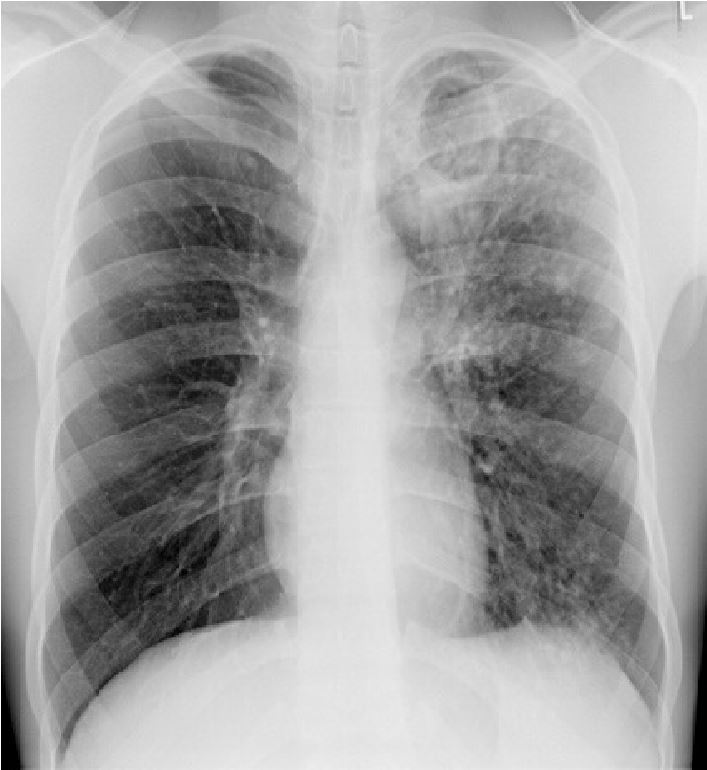

Volgens de wet is het noodzakelijk om bij röntgendiagnostiek van de thorax naar een eventuele zwangerschap te vragen (NVKF 2015). De thoraxfoto mag in de zwangerschap gemaakt worden, mits de uterus zich niet in de stralenbundel bevindt (Besluit stralingsbescherming 2001). In de praktijk kan dit voorkomen worden door goed te diafragmeren en te zorgen dat de uterus op minimaal 10 cm buiten de röntgenbundel ligt. In geval dat de genoemde veiligheidsmarge van 10 cm niet toegepast kan worden, dient de röntgendiagnostiek te worden afgewogen tegen de risico’s (Besluit stralingsbescherming 2001). Het radiologische beeld kan divers zijn. Het typische beeld van primotuberculose bij jonge kinderen bestaat uit een unilaterale hilaire lymfkliervergroting. Bij volwassenen komt vaker het typische beeld van infiltratieve afwijkingen voor, meestal in de bovenvelden, al dan niet met holtevorming. De holtevorming is het gevolg van een krachtige immuunreactie met granuloomvorming. Holtevorming en uitgebreide afwijkingen duiden meestal op al langer bestaande ziekte (zie figuur 1). Pleuravocht is meestal de enige uiting van pleuritis tuberculosa maar kan ook samenhangen met pulmonale tuberculose. Een typisch beeld van ernstige tuberculose is miliaire tuberculose, waarbij multipele kleine noduli zichtbaar zijn, uniform verspreid over beide longen.

Figuur 1: Thoraxfoto met een typisch dikwandige holte (caverne) in de linker bovenkwab en verspreid over de linker long kleine haardjes